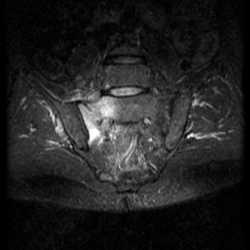

Мужчина, 60 лет. Направлен на МРТ пояснично-крестцового отдела позвоночника для исключения грыжеобразования. Жалуется на боли в правом тазобедренном суставе. Боли начались около месяца назад, сначала...